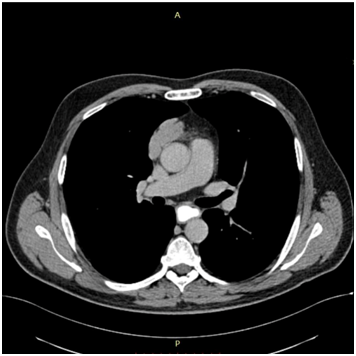

Bild 8 CT – axial plan of the seminoma.